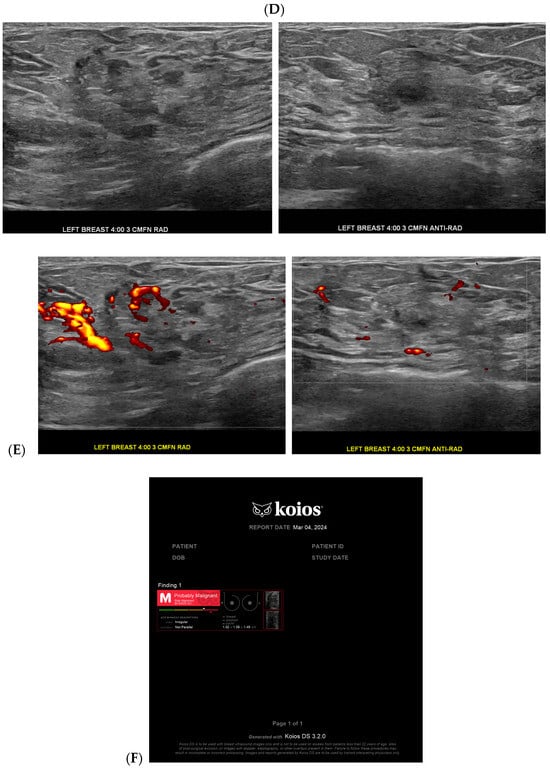

Figure 1.

Developing asymmetry detected by artificial intelligence (AI): Between the baseline screening mammogram (A) and the follow-up screening mammogram 17 months later (B), there has been a very subtle development of left breast asymmetry that is difficult to perceive with the naked eye. However, the AI program Transpara highlighted potential regions of interest (C) for the radiologist to query for additional mammographic and sonographic imaging. On further diagnostic imaging, the subtle asymmetry corresponds to a hypoechoic mass at left 4:00, 3 cm FN (D) with hypervascularity (E). AI program Koios correctly recognized the mass as “Probably Malignant”, and this area returned as a biopsy-proven invasive malignancy with lymphangitic spread (F). Images obtained from the Icahn School of Medicine at Mount Sinai.

Cancer detection systems typically involve neural networks, machine learning, or deep learning developed from training models to recognize patterns, while diagnostic systems use an additional algorithm to classify [17]. Several CNN models have been developed to correlate ultrasound imaging features of a lesion with the four-classification breast cancer molecular subtypes [42]. Our institution uses Koios, which utilizes machine learning and AI to generate the probability of malignancy of a breast finding by evaluating a region of interest (ROI) selected by a radiologist [3,5]. Ultrasound AI has been found to reduce intra- and interobserver variability and to improve accurate BI-RADS classification of sonographic breast findings [3,5]. Ultrasound AI can also increase CDR [5] and reduce the number of unnecessary biopsies [5,43,44] (Figure 1, Figure 3, and Figure 4).